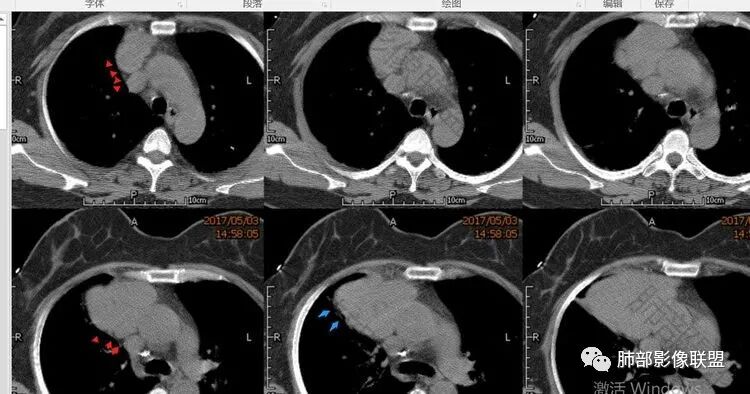

吴婧wj:

红色是掀开的胸膜,胸膜不是受压,定位前纵隔;蓝色是受压肺组织

有钙化应该不考虑淋巴瘤吧,还有年龄也不符合,淋巴瘤中心生长,这个偏侧,而且,胸腺瘤也不一定会坏死,淋巴瘤,是不符合的太多。其实强化也不符合,结节融合型他没有。弥漫大b他坏死不够,t母年龄不符。更别说还有钙化,诊断淋巴瘤是可能性太低